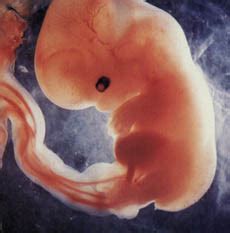

Pirmasis trimestras (1-13 savaitės):Šis laikotarpis yra pats jautriausias. Susiliejus sėklos ląstelei ir kiaušialąstei atsiranda nauja gyvybė. Užsimezgusio gemalo dydis - 0,12 mm. Tačiau genetinėje medžiagoje jau užkoduota, ar tai bus mergaitė ar berniukas, ar akys bus rudos kaip mamos, ar melsvos, kaip tėčio. Po keturių valandų gemalas ima dalytis - iš vienos ląstelės atsiranda dvi. Procesas jau prasidėjo - toliau ląstelės nepaliaujamai dalysis nuolat. Penkias dienas jau gerokai suapvalėjęs ląstelių gumuliukas kiaušintakiais keliauja į gimdą, ten jis pamažu įsitvirtina gimdos gleivinėje. Dar po kelių dienų nėštumo testas jau parodys, kad užsimezgė nauja gyvybė.

Penktąją savaitę ima plakti vaikučio širdis. Rankytės ir kojytės pūpso tarsi maži pumpurėliai. Dar po kelių dienų žmogutis jau netgi galės pasukti galvytę. Jau yra visų organų ir organų sistemų užuomazgos. Jūsų vaikelio judesiai dabar jau gana aiškūs. Krūtinės ląsta ritmingai kilnojasi, tarsi jis kvėpuotų. Jis jau sukiojasi ir rąžosi. Judėjimas labai reikalingas: tai, ką judėdamas patiria juslėmis, labai svarbu vaisiaus smegenų raidai.

Nėštumo metu (9-12-oje savaitėje) mažylio kepenys pradeda gaminti tulžies skystį. Trečiojo mėnesio pabaigoje vaikutis jau gurkšnoja vaisiaus vandenis, o paskui juos šalina. Rijimo judesiai treniruoja plaučius ir inkstus. Pradeda formuotis ir didžiųjų smegenų pusrutulių žievė. Mažylis jau dalyvauja jūsų gyvenime - jis jaučia susijaudinimą, pasitenkinimą, stresą. Jums išsigandus kraujyje padaugėja adrenalino - dėl to greičiau ima plakti ir mažylio širdelė.